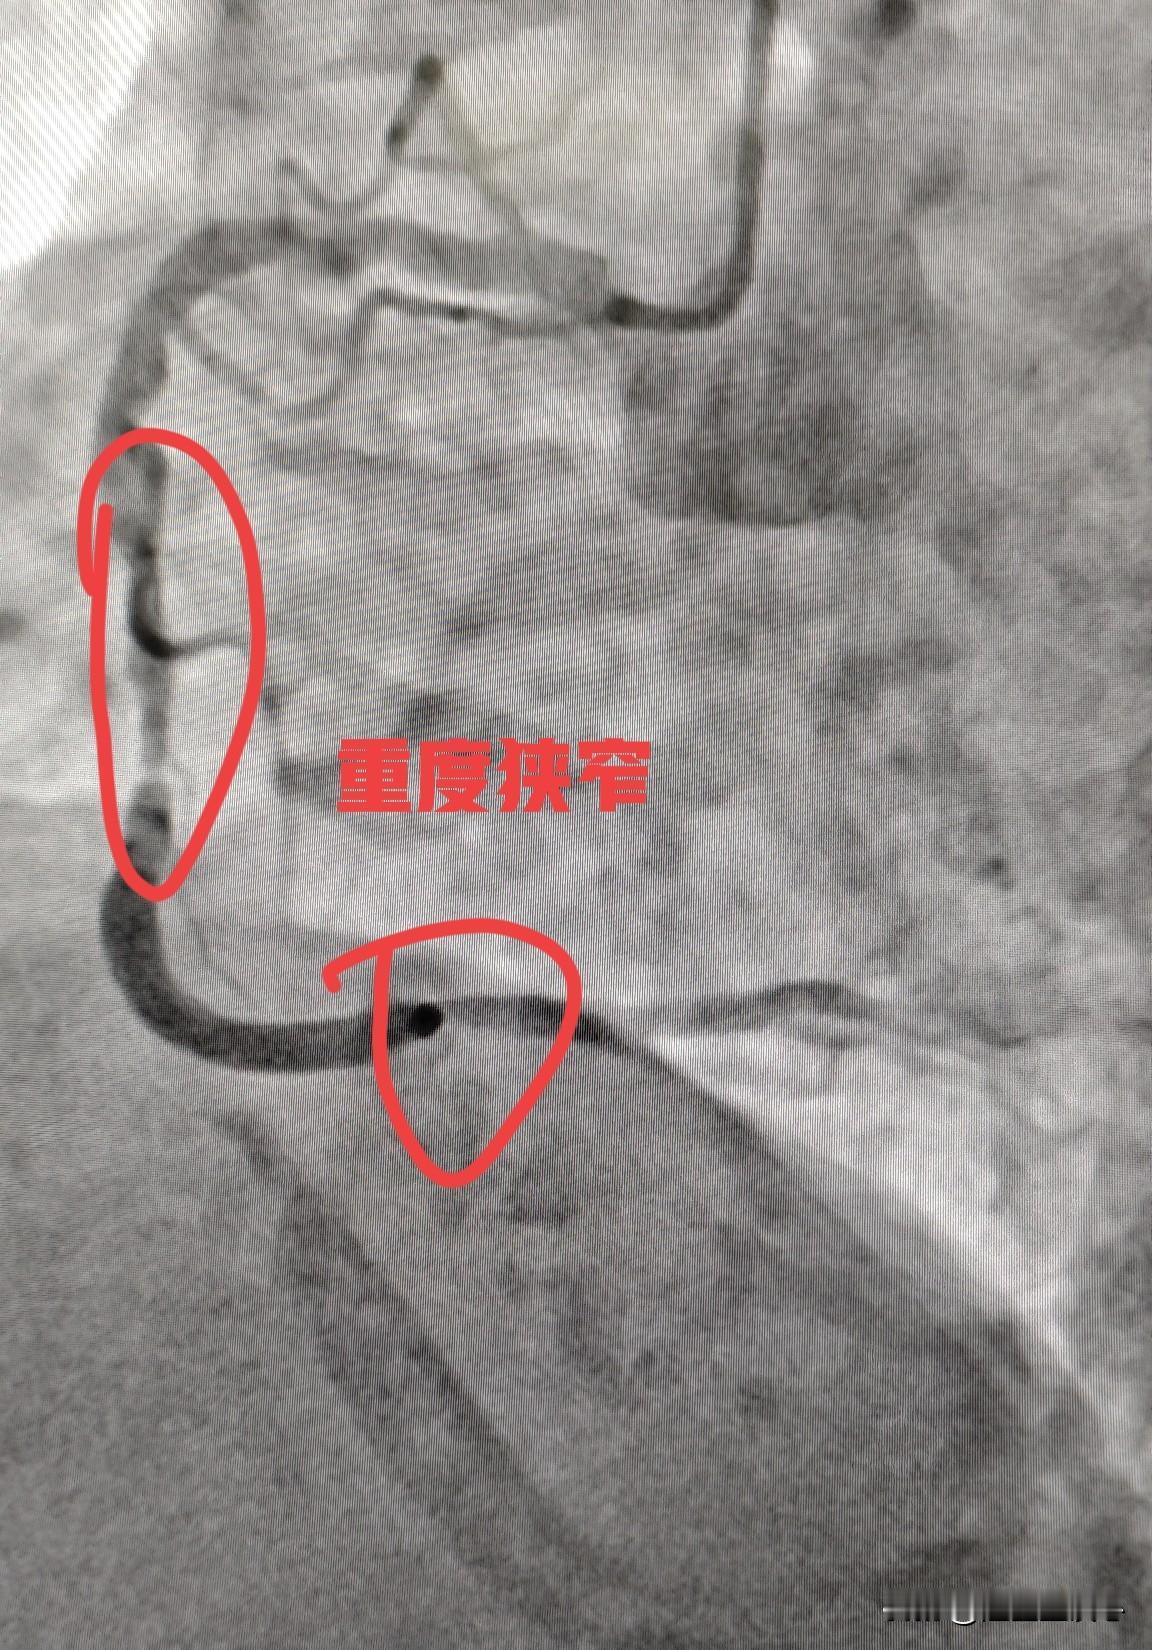

高龄女性,多根血管狭窄,耐受性差,低体重,分次手术更安全。75 岁女性患者,三支病变,前降支长节段重度狭窄,回旋支闭塞,右冠重度狭窄。 回旋支细小,供血范围相对比较小,有侧支循环,战略性放弃,就不开通了。主要精力放在右冠和前降支上面。 考虑到患者高龄,耐受性差,造影剂量大以后会影响到肾脏,引起肾功能恶化。今天先右冠做了2 枚支架。让患者休息一段时间后,身体休养一下。过段时间再来做前降支。